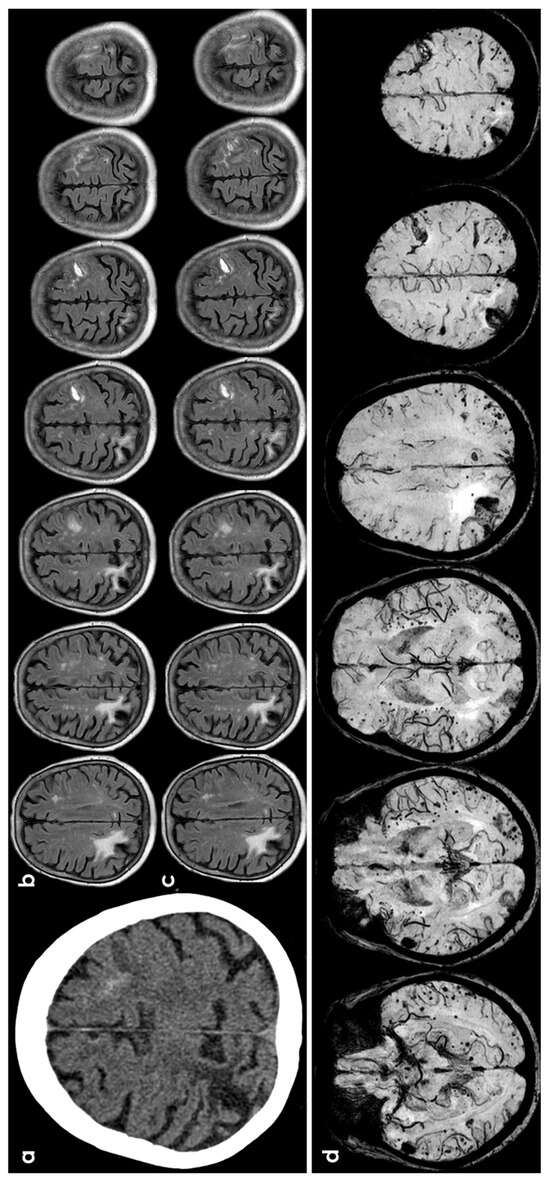

3.1. CAA

3.5. Primary Central Nervous System Angiitis

3.6. PRES/RCVS